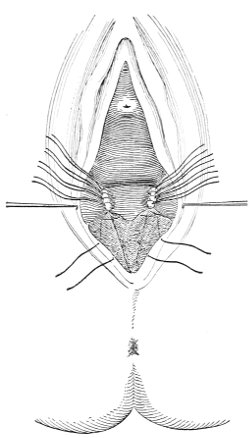

Slight Median laceration of the Perineum.—In this injury the tear takes place through the fourchette. Posteriorly it may extend as far as the sphincter ani muscle. Upward it may extend for an inch up the posterior vaginal wall. The appearance of this tear is shown in Fig. 33. It will be noted that, as this tear takes place in the median line, none of the muscles that support the perineum are involved, nor are the planes of fascia injured. The perineum is slightly split, and the insertions and origins of the muscles and the fascia are slightly separated. The supporting structures of the perineum and the pelvic floor are, however, uninjured.

Fig. 33.—Recent slight median laceration of the perineum: sutures introduced.

If this tear is detected after labor, it should be closed by the immediate operation. A slight tear involving chiefly the cutaneous aspect of the perineum should be closed by three or four sutures introduced from the outside, as in Fig. 33. The needle should be introduced about a quarter of an inch from the edge of the wound. It should not be passed parallel with the plane of the lacerated surface, but should be swept outward and then inward toward the 68 angle at the bottom of the tear (Fig. 34). It may either emerge at the angle and be re-introduced, or it may be passed directly through to the skin-margin on the opposite side of the wound. If the suture is passed in this way, there will be perfect apposition throughout the whole surface of laceration. If the sutures are improperly passed, there may result only apposition of the skin-edges.

Fig. 34.—Diagram representing the correct and the incorrect method of passing the suture for closure of slight perineal laceration.

If the laceration extends up the posterior vaginal wall, two sets of sutures must be introduced—one on the vaginal aspect of the tear, and one on the skin aspect (Fig. 35).